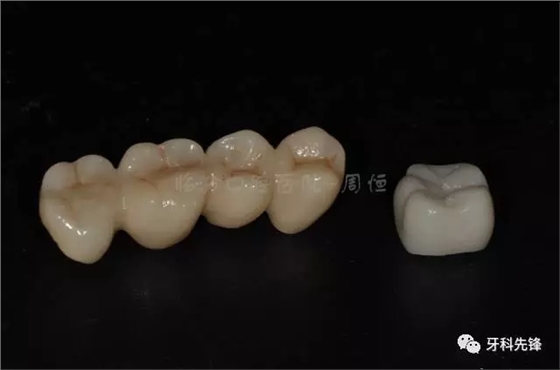

圖7原烤瓷冠修復(fù)體

640.webp (8).jpg

640.webp (9).jpg